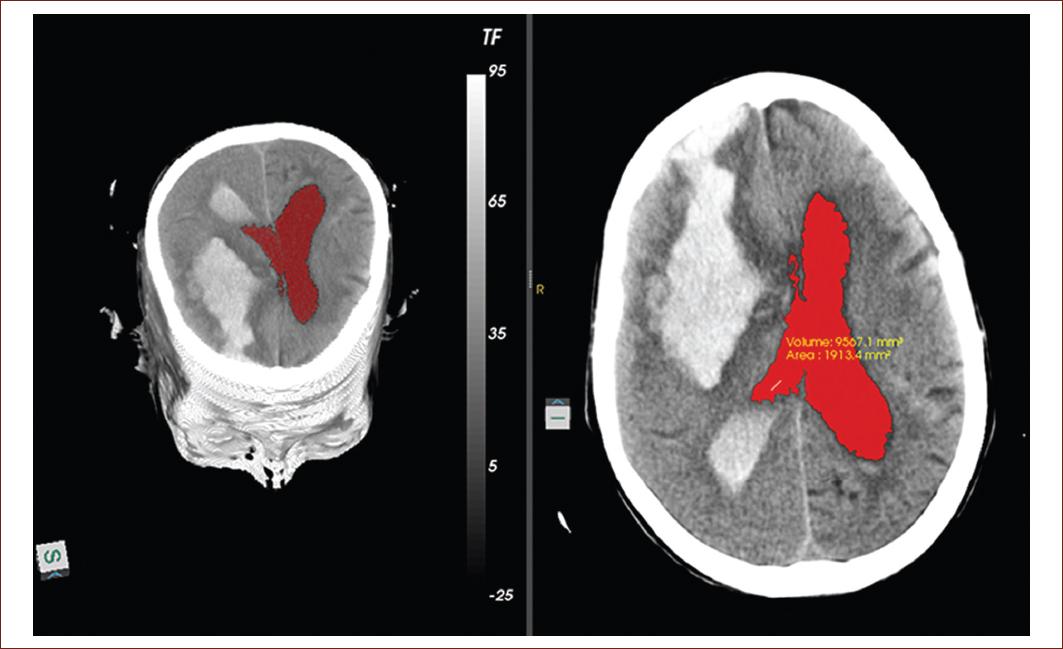

For many clinical tasks such as surgical planning, it is necessary to understand and communicate complex and often malformed 3D structures and it is achieved through neuroimaging. Experience has shown that mental reconstruction of objects from cross-sectional images is extremely difficult and highly dependent on the observers training and imagination. For these cases, it is advantageous to present the human body as a surgeon or anatomist would see it (Fig. 4)38.

Figure 4 Left image: represent the three-dimensional reconstruction from the segmentation of the lateral ventricles and the volume 9988.4 mm3 and area 1977.7 mm2 obtained in this tomography slice, were the hemorrhagic focus of 82 front parietal right UH is observe in the right image (source: taken from the Imaging Department, Juan Bruno Zayas Alfonso Hospital).